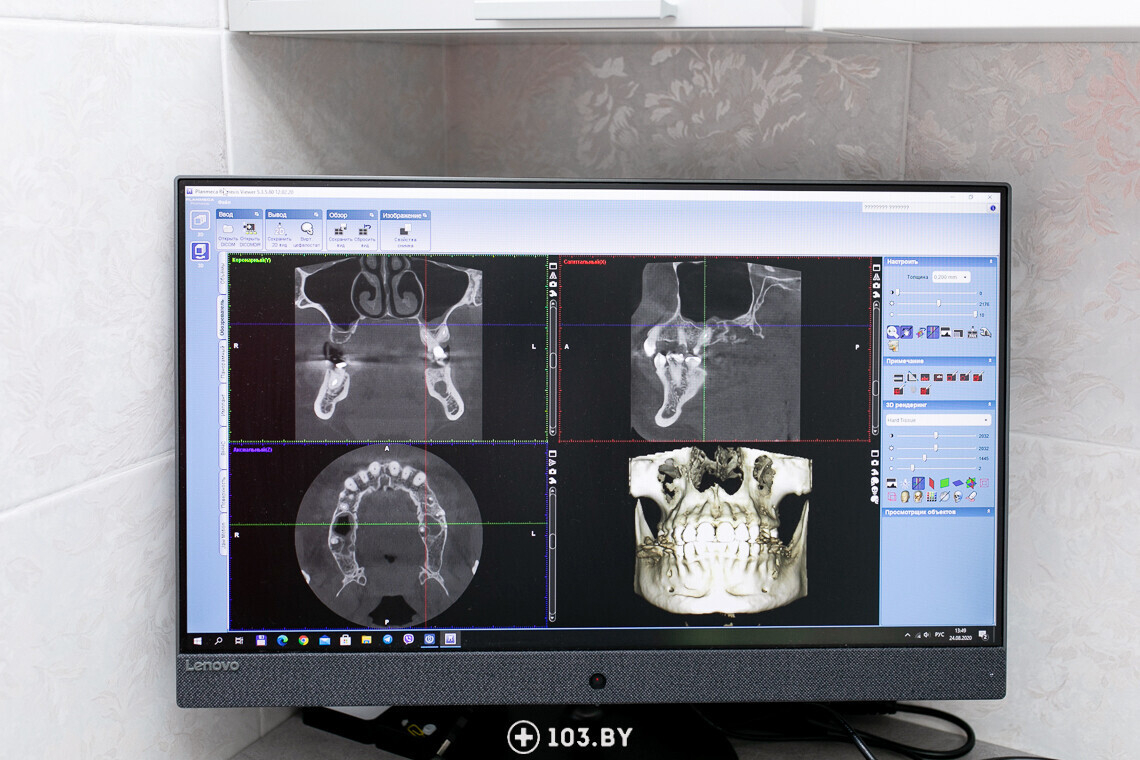

Кстати, сегодня у врачей есть возможность сделать 3D-снимок челюсти. Он помогает специалистам детально подготовиться к имплантации и учесть все нюансы.